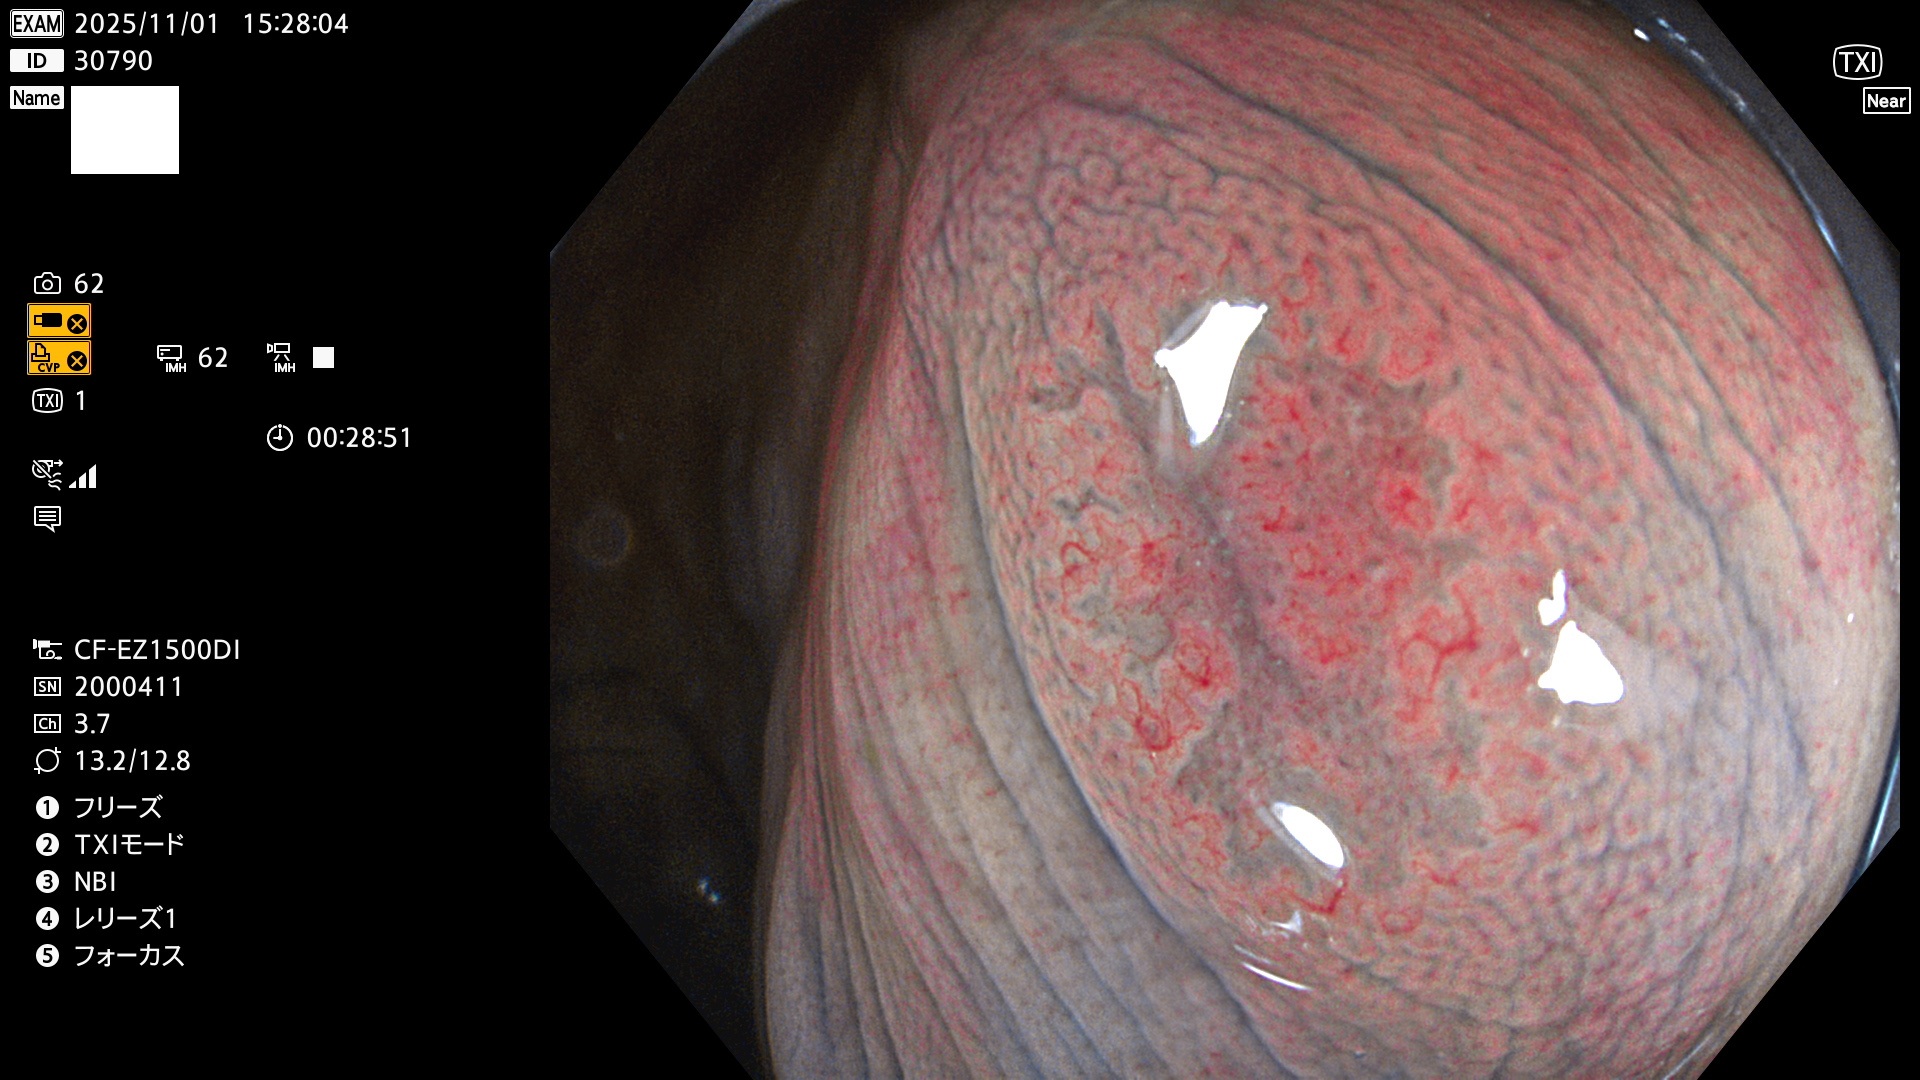

毎週の検査(木・金・土・日)に発見されたUbとUc型・腺腫を、その週の日曜の夜にUPし1週間、提示します。

写真公開の目的は「透明性・信憑性の担保」ですが、公開を希望されない方はメールで御連絡下さい。直ちに削除いたします。

2025年10月30日〜11月2日の4日間(40件)9個 (Uc_ADR=9個/40人=23%)